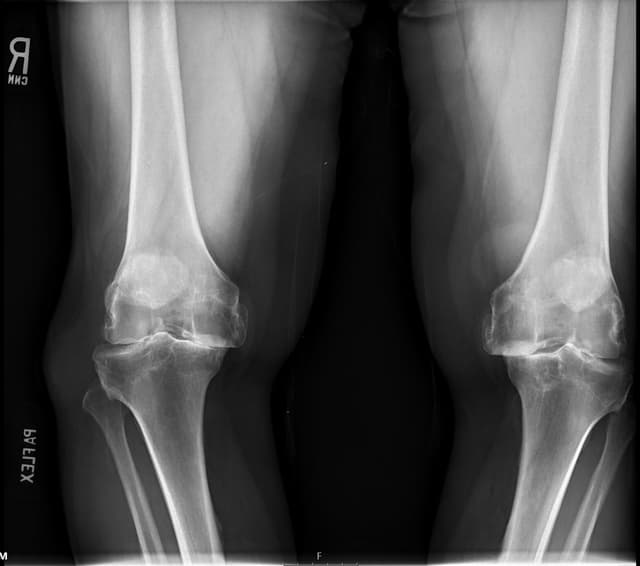

Total Knee Arthroplasty (Cementless, Robotic-assisted)

Imaging

Pre-op